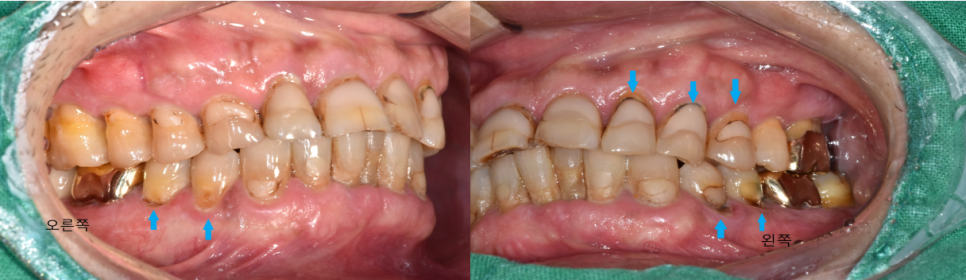

치아 정면사진을 보시면 치아 목부위가 많이 깨져있고

기존에 치아 목부위 치료를 많이 받으셨던걸 보아 저작하는 힘이 강하고

전반적인 구강위생관리가 미흡하고

흡연을 하시는걸 알 수 있었습니다.

임플란트를 식립하기 위해 기다리는 동안 신경치료를 마무리 하고

전체적인 잇몸치료도 같이 진행하면서 구강관리 위생교육과 잇솔질 교육도 같이 진행 해드렸습니다.

(잇몸치료란 ?

먼저, 전체적으로 스켈링을 통해 치아전체를 깨끗하게 청소한 뒤에

4부위 또는 6부위로 나누어 국소 마취후 수기구를 통해

손으로 직접 잇몸 하방에 있는 치석과 염증을 긁어내어

잇몸이 좀 더 튼튼하고 단단해 질 수 있게 합니다.